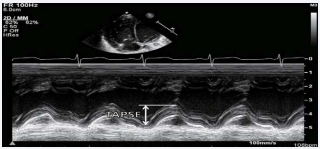

TAPSE

It is easily available and is a measure of RV longitudinal function. TAPSE < 16 mm indicates RV systolic dysfunction [1]. It is evaluated from the tricuspid lateral annulus (Figure 7).

Figure 7: Measure of Tricuspid annular plane systolic excursion (TAPSE).

Though it evaluates longitudinal function, it has shown good correlation with techniques estimating RV global systolic function, e.g. radionuclide-derived RV EF, 2D RV FAC, and 2D RV EF.